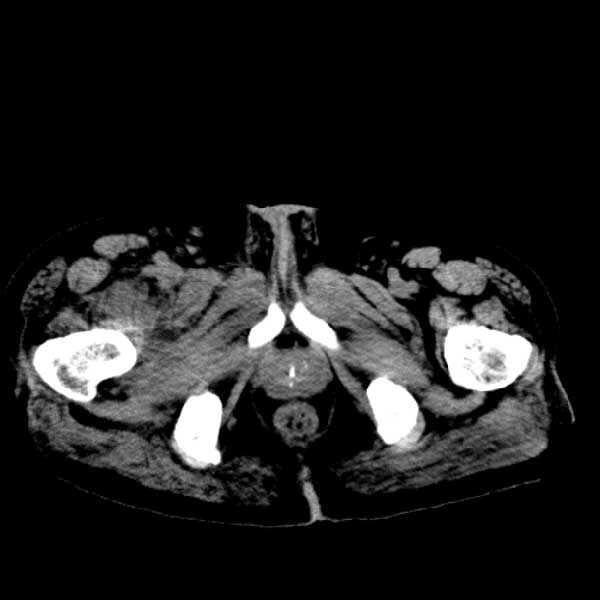

标题: CT13513:男 71 腹部疼痛20余天,近几天高热就诊,骨窗未见异 [打印本页]

标题: CT13513:男 71 腹部疼痛20余天,近几天高热就诊,骨窗未见异

考虑感染性病变可能性大,起源于阑尾?

感染,脓肿形成

考虑为化脓性阑尾炎.脓肿形成.及多肌肉累及.

考虑右侧腰大肌脓肿,向右髂窝、右腹股沟流注。

支持化脓性阑尾炎伴右髂窝脓肿、腰大肌腰方肌脓肿形成。

考虑腹腔及盆腔化脓性炎症,累及右侧髋关节及腹股沟区.

首先考虑化脓性阑尾炎伴腰大肌、腰方肌脓肿,不除外回盲部结核。

回盲部癌待排除。

患者肠镜检查考虑结肠癌,病理证实

患者肠镜检查考虑结肠癌,病理证实。肺部ct可见多发结节,考虑转移